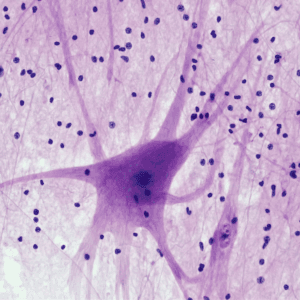

Especialistas en Enfermedades Autoinmunes, enfermedad de LYME y tratamientos orientados a la Longevidad Biológica.